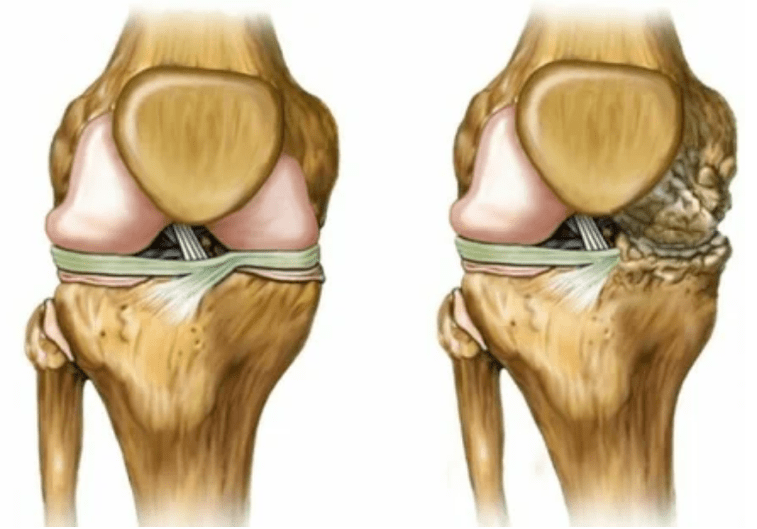

- 3 grados. A menudo hay dolores, es difícil mover la extremidad debido a los cambios en la articulación. Las lesiones son extensas, se vuelven notables a la apariencia desnuda. Se produce la deformación del sitio articular, el área afectada se hincha y se vuelve roja. El eje de la extremidad está perturbado, lo que conduce a la complejidad del movimiento. Los cambios patológicos provocan acortar los ligamentos. Aparecen subluish y contracturas. Los músculos adyacentes se acortan o estiran, de los cuales se debilita la función contráctil.

deformaciones de la extremidad. Aparece en una forma descuidada de la enfermedad, indica la destrucción completa del tejido del cartílago y la aparición de osteofitos. En este estado, aumenta la presión sobre las articulaciones en la parte superior y inferior, desde la cual la curvatura puede afectar toda la extremidad.

Es importante recordar que la deformación de los huesos en la pierna a menudo se confunde con el maíz. El síntoma es poco peligroso solo a primera vista, pero conduce a graves consecuencias.